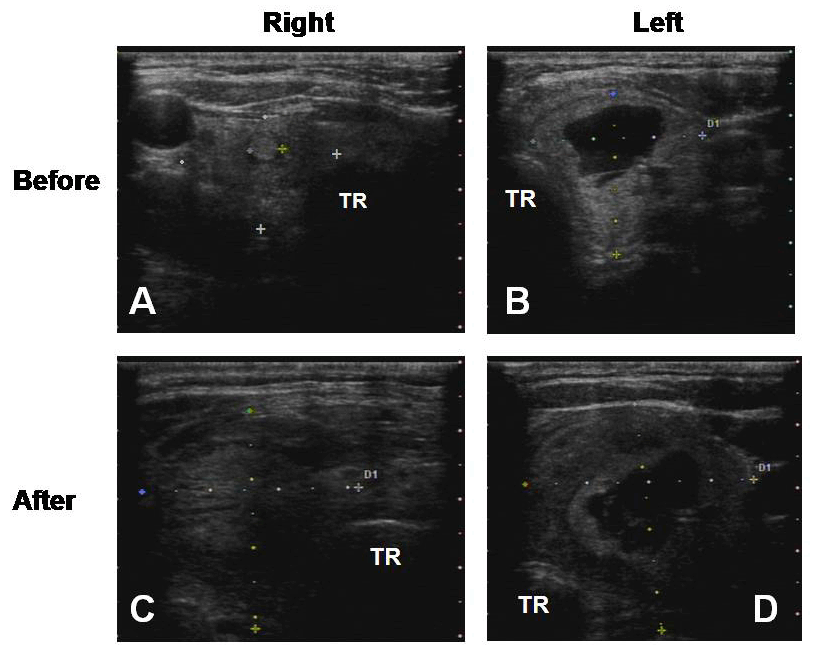

From radiologykey.com

FineNeedle Aspiration Biopsy of Thyroid Nodules Radiology Key How Painful Is A Needle Biopsy Of The Thyroid Find out when you might. the biopsy site may be sore and tender for 1 to 2 days. core needle biopsy: this article will discuss why you may need a thyroid biopsy, what it means to have a fine needle aspiration, if. How long does a thyroid biopsy take? This care sheet gives you a general idea. How Painful Is A Needle Biopsy Of The Thyroid.